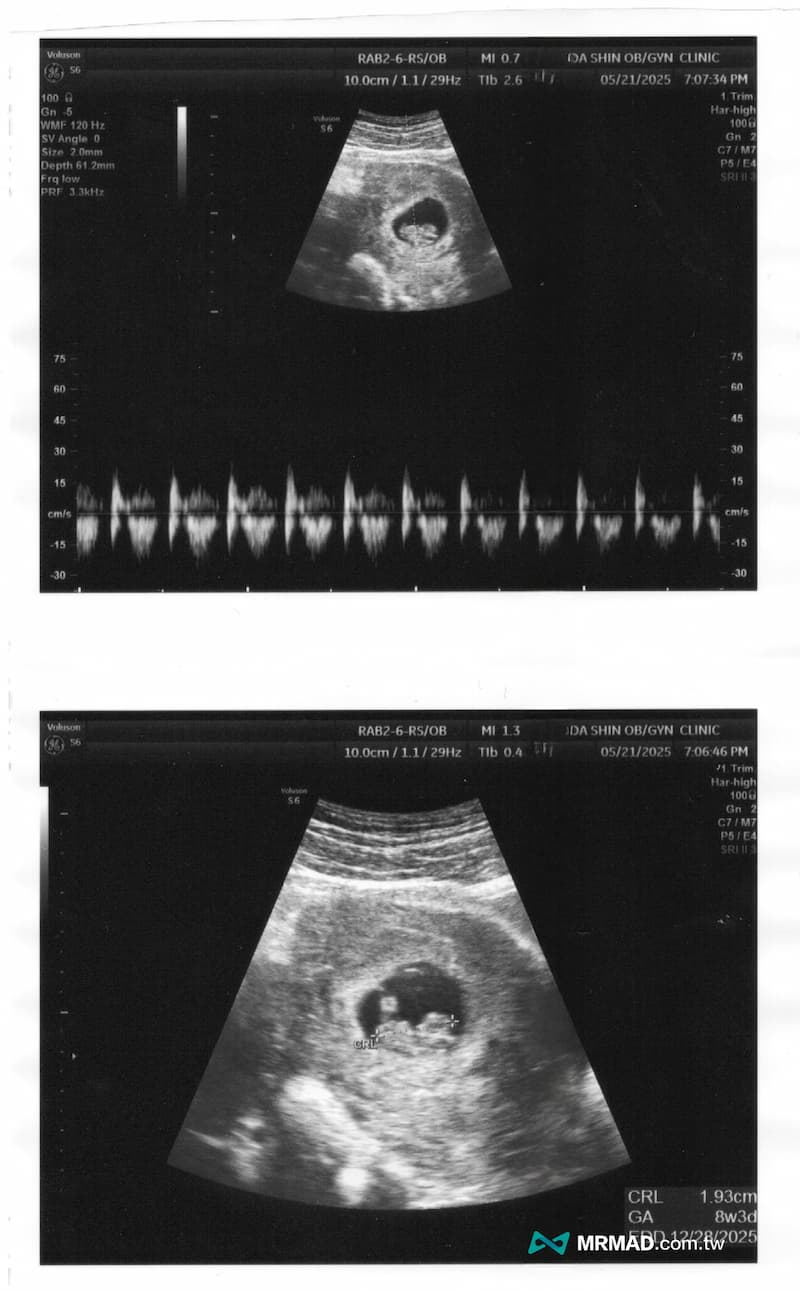

後續就依照時間陪老婆回去產檢,直到在超音波那端出現小小的光點,畫面中的小生命也隨著發出「咚、咚、咚」規律很有力的心跳聲音,那時候心裡馬上浮出一個念頭「謝謝你,選擇來到我們身邊。」,才真正感覺到我要當爸爸了!

一個小生命的誕生,而且他的心跳這麼奮而有力跳動,這比起入手一台全新iPhone或特斯拉會更有成就感,就像是人生解鎖新成就,對於我來說,人生在世如同打怪升等,需要不斷有新的挑戰目標,才不會留下任何遺憾。

從試管一路走來確實真的辛苦,就算挨針吃藥都是媽媽,但對於爸爸來說,在看見小孩的心跳聲那一刻全都化成眼淚,這些都不是電影情節,也不是別人的故事,而是專屬於我們的奇蹟。